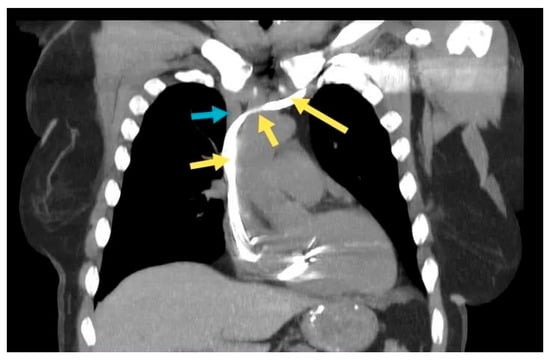

2.2. Case 2. (Type IIIa)